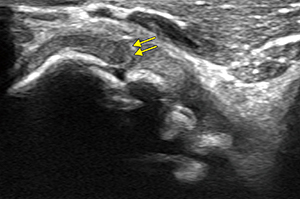

岩本部長が、Aplio i800でこだわり、一番のターゲットとしているのが肘関節の軟骨の描出である。岩本部長は、NPO法人(江戸川スポーツ医学研究会)で少年野球選手を対象とした野球肘検診にも取り組んでいる。野球肘は投球障害肘とも呼ばれ、投球動作によって生じる筋や腱、靭帯などの障害や骨軟骨の外傷・障害である。部位によって、内側障害 、外側障害、後方障害に分類されるが、外側の離断性骨軟骨炎は軟骨やその下の骨がはがれることで、疼痛やロッキングなどの障害が発生する。離断性骨軟骨炎は、初期であれば保存的治療を行い経過観察を行うが、軟骨が剥離するなど進行している場合には手術が必要となる。岩本部長は多くの野球肘の症例を診療する中で、「従来の超音波診断装置では、軟骨部分は黒くなっていて内部の状態はわかりませんでした。軟骨の下にある骨(軟骨下骨)の状態を確認していましたが、Aplio i800では軟骨の内部が濃淡のある画像として確認できました。特に子どもの肘関節は軟骨が厚く、内部の状態がわかれば手術適応など治療方針の決定に寄与することが期待されます」と説明する。さらに、「スポーツ選手の診療で重要なポイントとなるのが競技復帰時期の判断です。いつから復帰できるのか、どの程度練習に参加してよいのかは選手にとっては重要な問題で、その判断のための情報は多い方がより適切な判断ができます。Aplio i800の高画質画像が有効な情報になるのではと考えて、症例を蓄積しながら検討しているところです」と述べる。

図1 離断性骨軟骨炎(野球肘) |